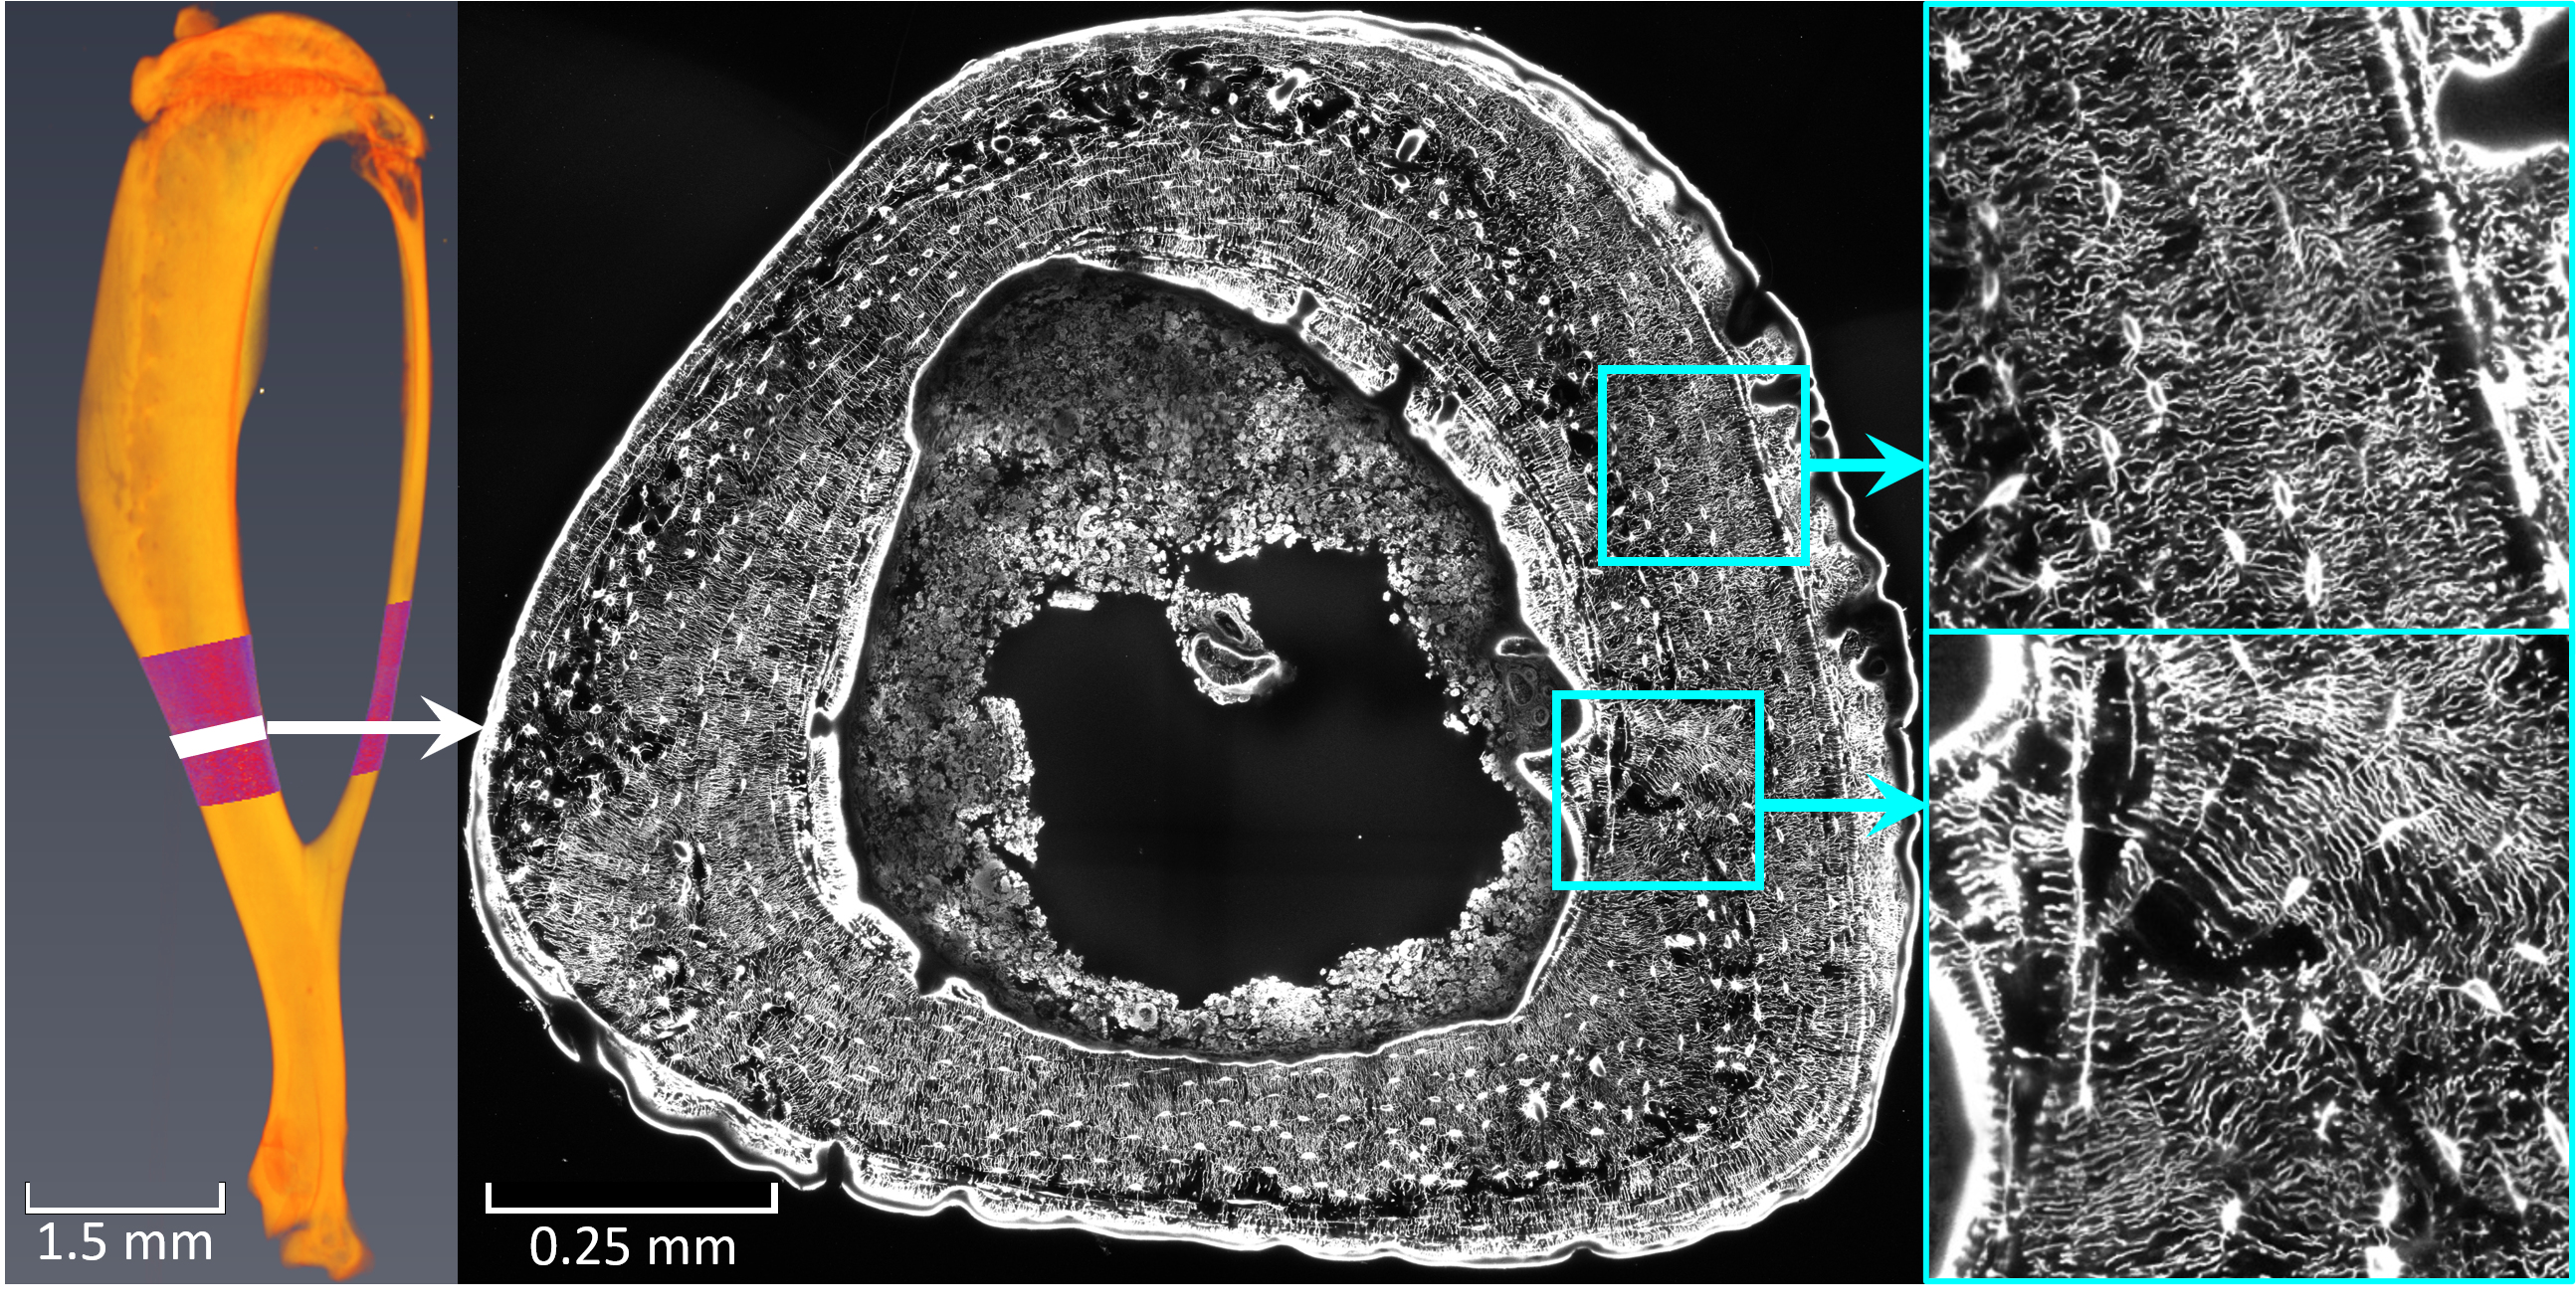

Knochen lassen sich wie ein Muskel trainieren. Im Zuge der Studie untersuchten Forscher in Montreal Mäuseknochen, die ein kontrolliertes „Knochentraining“ durchlaufen haben. In Potsdam nutzten Weinkamer und sein Team konfokale Laser-Scanning-Mikroskopie, um das Zellnetzwerk der trainierten Knochen in 3D abzubilden. Diese Bilddaten verwendeten sie zur Analyse und Bewertung von Netzwerken mit Millionen von Kanälen mittels Computersimulationen, die den Flüssigkeitsfluss durch das Netzwerk berechnen: „Auf Grund unserer Ergebnisse, sind wir überzeugt, dass die Knochenzellen innerhalb der Netzwerke den Flüssigkeitsfluss wahrnehmen können, miteinander kommunizieren und so Informationen wie ‚Knochenwachstum‘ an andere Zellen weitergeben“, sagt Alexander van Tol. Er fügt hinzu: „Die untersuchten Mäuse haben unterschiedlich stark auf das Knochentraining reagiert. Eine Maus, die besonders wenig neuen Knochen produziert hat, verfügt über ein Netzwerk, dessen Architektur nur einen langsamen Flüssigkeitsfluss zulässt.“ Er ergänzt: „Daher glauben wir, dass auch für den Menschen gilt: Knochen lässt sich durch sportliche Betätigung besonders gut kräftigen, wenn die Netzwerkstruktur innerhalb des Knochens ,mitspielt‘.“ Mit dieser Studie erfolgte erstmals eine Bewertung der Qualität der Netzwerkarchitektur in Bezug auf die Wahrnehmung mechanischer Reize.